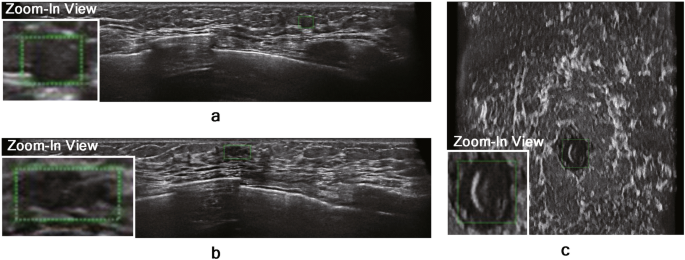

The TP results on the in-house ABUS dataset A and B are illustrated in Figs. 5 and 6, respectively. The nodules with relatively large sizes are easily distinguishable from the background tissue (see BI-RADS categories 4 and 5 cases in Figs. 5 and 6). Even the relatively small nodules in BI-RADS category 3 show clear separation from the background tissue for TP results. Figure 7 illustrates the FP results on the in-house ABUS datasets. The FP results include the detection of fat lobules, acoustic shadowing, and nipple, where the fat lobules and acoustic shadowing are the majority of FPs.

TP results on the in-house ABUS dataset A. (a) BI-RADS category 3 case. (b) BI-RADS category 4 case. (c) BI-RADS category 5 case. Images are arranged in the order of transverse, coronal, and sagittal views in a downward direction. Blue boxes with a thick solid line show the ground truth bounding box, and red boxes with a thin solid line show the TP detection.

TP results on the in-house ABUS dataset B. (a) BI-RADS category 3 case. (b) BI-RADS category 4 case. (c) BI-RADS category 5 case. Images are arranged in the order of transverse, coronal, and sagittal views in a downward direction. Blue boxes with a thick solid line show the ground truth bounding box, and red boxes with a thin solid line show the TP detection.